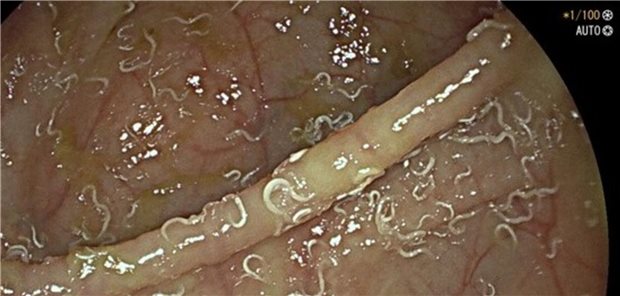

Die extraintestinale Manifestation einer Infektion mit Enterobius vermicularis ist eine Rarität. Weltweit gibt es sechs Berichte eines Leberbefalls mit dem Erreger. Ein Fallbericht aus Leipzig.